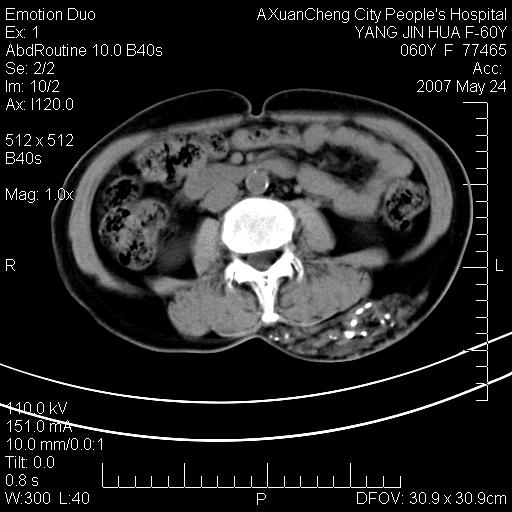

发现左侧腰背部包块40余年,逐渐长大,质软,局部表面可见扩张的血管影

左背部皮下良性肿瘤,密度不均,边界不清,内有脂肪、钙化,增强扫描无明显强化,血管平滑肌脂肪瘤?进一步诊断有困难,建议穿刺活检。

左侧背部皮下混杂密度肿块,结构较疏松,边缘欠光整,内有多发斑点状钙化,考虑:皮下血管瘤。

左背部皮下良性肿瘤,密度不均,边界不清,内有脂肪、钙化,增强扫描无明显强化,血管平滑肌脂肪瘤?进一步诊断有困难,建议穿刺活检。还有,我想还是问一下病史,患者有外伤史吗?能否完全排除外伤后机化的....

血管平滑肌脂肪瘤,支持!另应详细了解病史,待除外骨化性肌炎。

1.考虑左腰部皮下平滑肌脂肪瘤可能性大;

2.位置特殊,不除外畸胎瘤及错构瘤可能;

3.另骨化性肌炎应在考虑范围之内,请追问病史;